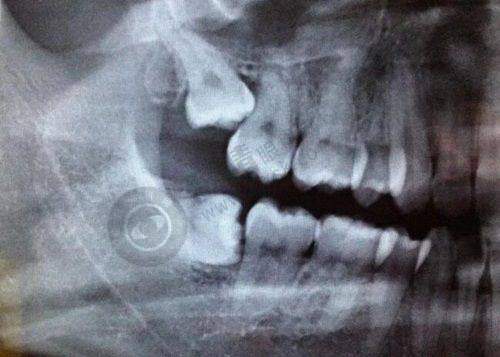

清远粤美口腔采用精良的数字影像技术,通过三维模型的建立来精细评估患者的牙齿问题,减少误差,大大提高了矫正成效。这种精良的技术能够让医生更正确地了解患者的口腔状况,制定出更合适的治疗方案。